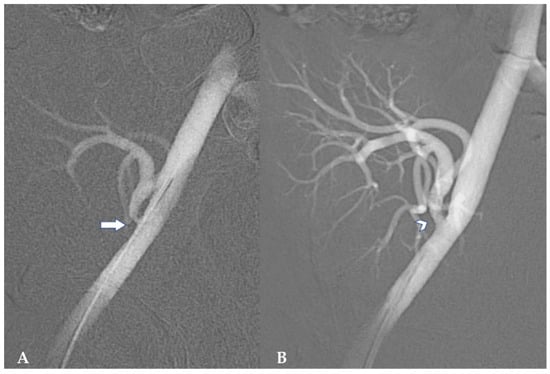

Management of Surgical Complications in Pediatric Kidney Transplantation

Introduction: Graft and patient survival after kidney transplantation in children has increased in the past decade; however, post-transplant surgical complications occur in up to 15.4% of recipients and pose a significant threat to graft survival. Due to anatomic discrepancies in children, kidney transplantation in this population is nuanced and requires meticulous planning. This narrative review summarizes the most common postoperative surgical complications following kidney transplantation in children. Methods: PubMed and Google Scholar were queried for full-text articles that reported pediatric kidney transplantation surgical complications and their management following kidney transplantation. Results: Vascular complications can occur in approximately 1.3–13.8% of cases and are the leading cause of graft nephrectomy, with arterial stenosis and venous thrombosis being the most common. Urologic complications occur in 1.3–30% of patients and are more frequent in children due to pre-existing genitourinary abnormalities prior to transplantation. Vesicoureteral reflux is the most common urologic complication. Discussion: Surgical complications following kidney transplantation in children continue to significantly affect graft viability. Ultimately, meticulous surgical techniques and close postoperative surveillance are critical to mitigating the risk of allograft nephrectomy. Prospective studies focused on best surgical practice, techniques, prevention, and postoperative care in pediatric kidney transplant recipients are needed. Full article

Show Figures

Figure 1